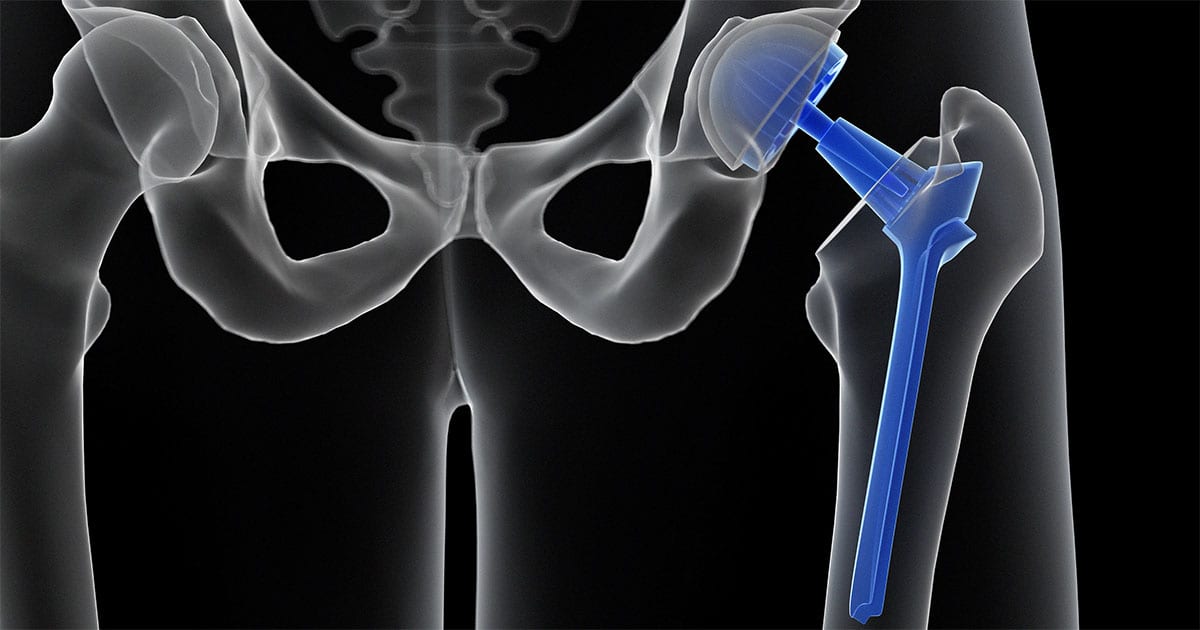

Total Hip Replacement BJISG

Partial Hip Replacement